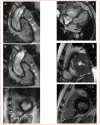

Rhythm and conduction disturbances and sudden cardiac death are important manifestations of cardiac involvement in autoimmune rheumatic diseases (ARD), which have a serious impact on morbidity and mortality. While the underlying arrhythmogenic mechanisms are multifactorial, myocardial fibrosis plays a pivotal role. It accounts for a substantial portion of cardiac mortality and may manifest as atrial and ventricular arrhythmias, conduction system abnormalities, biventricular cardiac failure or sudden death. In patients with ARD, myocardial fibrosis is considered to be the hallmark of cardiac involvement as a result of inflammatory process or to coronary artery occlusive disease. Myocardial fibrosis constitutes the pathological substrates for reentrant circuits. The presence of supraventricular extra systoles, tachyarrhythmias, ventricular activity and conduction disturbances are not uncommon in patients with ARDs, more often in systemic lupus erythematosus, systemic sclerosis, rheumatoid arthritis, inflammatory muscle disorders and anti-neutrophil cytoplasm antibody-associated vasculitis. In this review, the type, the relative prevalence and the underlying mechanisms of rhythm and conduction disturbances in the emerging field of cardiorheumatology are provided.